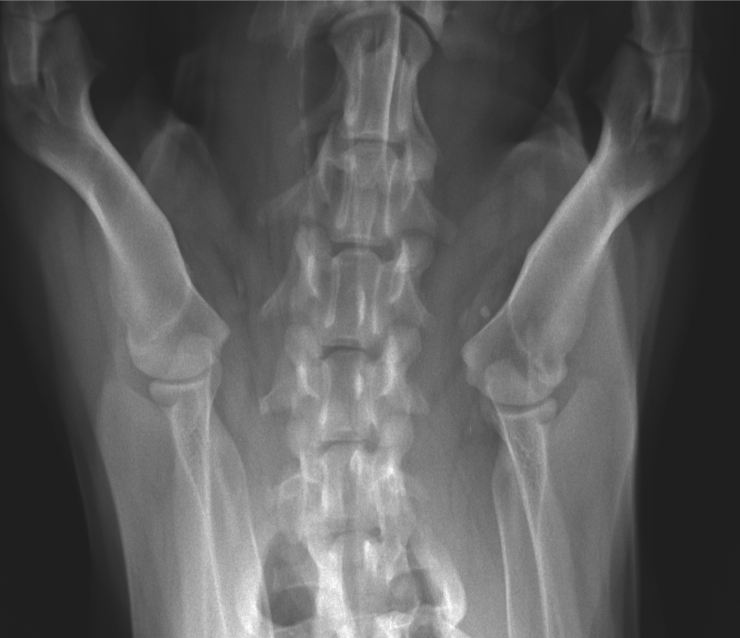

Histoire clinique: Dysphagie, douleur au cou, boiterie de non appui MTG, parésie MPs pire a gauche. Lésion suspectée au niveau cervical caudal latéralisée à gauche.

La lésion semble localisée au niveau de l’atlas. Serait-ce une fracture de cette vertèbre cervicale qui entraîne une dysphasie par compression de l’oesophage et douleur au courant? Si fracture il y a, quelle en serait la cause ? Est-ce que la compression de la moelle épinière à ce niveau pourrait être responsable de la paresie des MPs et de la boiterie de non appui au MTG?

Salut Robert ! La forme de l’atlas est due à sa rotation axiale, entraînant les ailes dorsalement et ventralement. C’est pour ça aussi que le processus odontoïde est si évident. On peut donc dire que ce processus est intact. Continue ton exploration des images… 😉